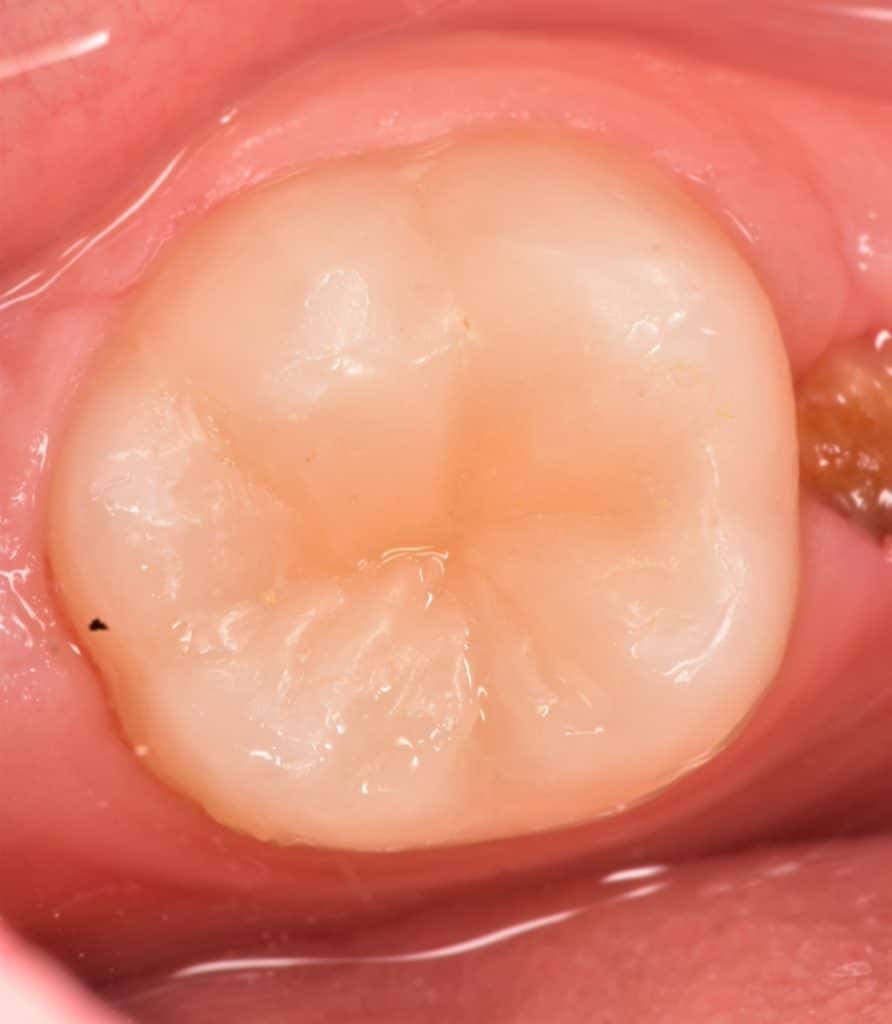

Occlusal view

Ever X posterior for dentin replacement , G-aenail Composite for enamel replacement , immediate result

Immediate result before finishing and polishing

Final result

One week follow up 🙏